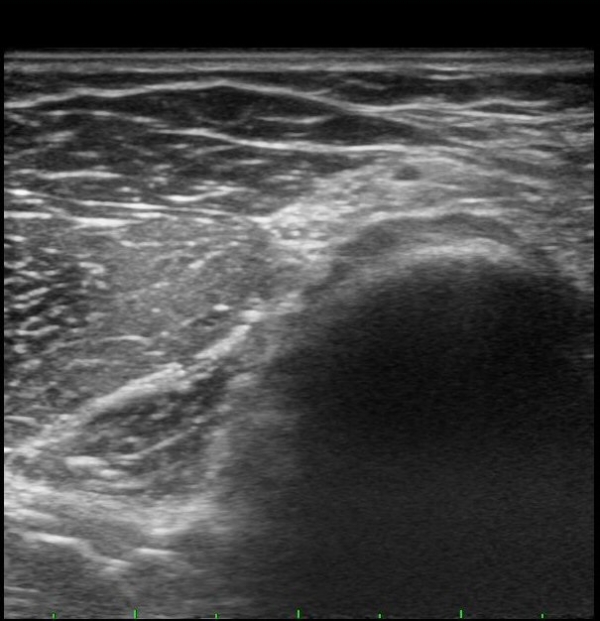

ÆÈ²ÞÄ¡ ¾ÕÂÊ È¾´Ü¸é°Ë»ç¿¡¼­ Èİñ°£½Å°æ(PIN)ÀÌ ¿ä°ñµÎ Àü¹æ¿¡¼­  Á¤»óÀûÀ¸·Î °üÂûµÊ(±×¸² 1).

ŽÃËÀÚÀ» ¸»´ÜÀ¸·Î À̵¿ÇÏÀÚ Èİñ°£½Å°æÀÌ È¸¿Ü±Ù ±ÙÀ§ºÎ¿¡¼­ Àú¿¡ÄÚ ºÎÁ¾À» º¸ÀÓ(±×¸² 2).

ŽÃËÀÚ¸¦ Á» ´õ ¸»´ÜÀ¸·Î À̵¿ÇÏ´Ï Èİñ°£½Å°æÀÌ È¸¿Ü±Ù ¸»´Ü¿¡¼­ Ç¥ÃþÀ¸·Î ³ª¿À´Â °ÍÀÌ °üÂûµÊ(±×¸² 3).

¾Æ·§ÆÈÀ» ȸ³» À§Ä¡¿¡¼­ Èİñ°£½Å°æ Á¾´Ü¸é°Ë»ç¸¦ ½ÃÇàÇÏ´Ï Èİñ°£½Å°æÀÌ µÎ ȸ¿Ü±Ù »çÀÌ¿¡¼­ ¾Ð¹Ú¹Þ°í ȸ¿Ü±Ù ±ÙÀ§ºÎ¿¡¼­ Àú¿¡ÄÚ ºÎÁ¾ÀÌ °üÂûµÊ(±×¸² 4, 5).